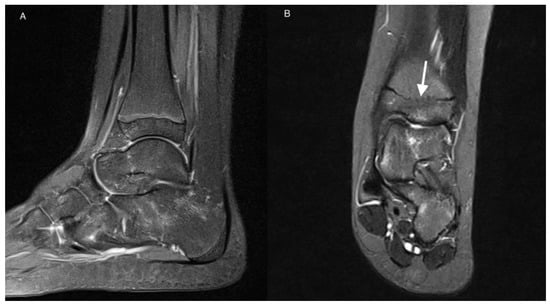

| 27 | Bone erosion | |||

| 0 | 20 (91%) | 22 (100%) | 0.469 | |

| 1 | 2 (9%) | 0 (0%) | ||